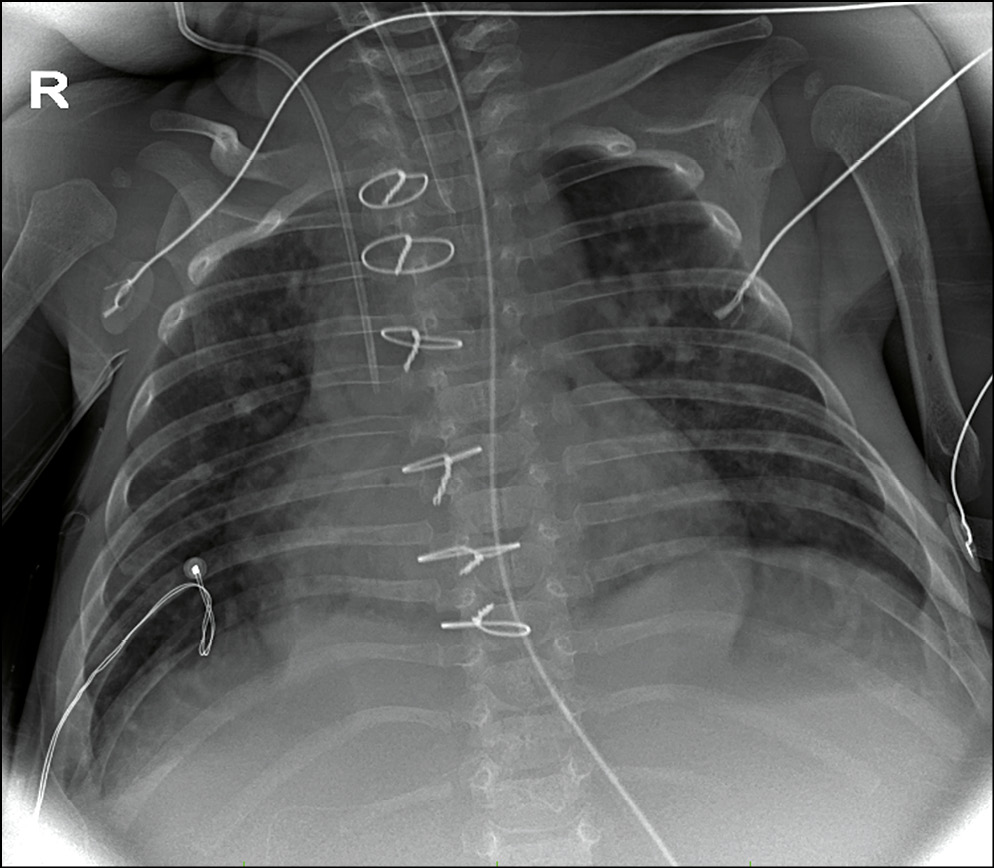

При респираторном дистресс-синдроме, наиболее распространенной причине дыхательных расстройств у недоношенных новорожденных, определяются диффузные участки усиления легочного рисунка за счет интерстициального компонента; прослеживается симптом «воздушной бронхограммы»; уменьшается объем легких (рис. 3).

Рис. 3. Пациент с респираторным дистресс-синдромом. Исследование выполнено при помощи микрофокусного рентгеновского аппарата.

Fig. 3. Patient with respiratory distress-syndrome. Microfocus X-ray device.